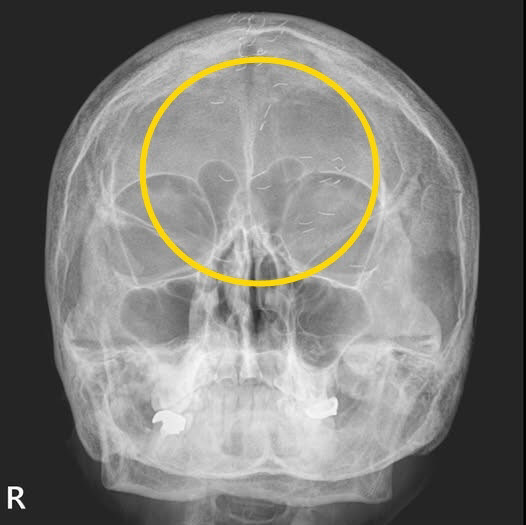

의사가 공개한 60대 여성의 머리 엑스레이 사진이다. (사진=양성관 가정의학과 전문의 SNS 캡처) |

양 의사는 “엑스레이에서 1cm 크기의 다수의 이물질이 발견됐다”며 “기생충인가? 전기칩인가? 외국이었다면 특이한 환자 사례로 ‘케이스 리포트’에 올랐을 것“이라고 사진을 소개했다.

그는 “그러나 한국 의사들은 보자마자 헛웃음을 짓는다”며 “이물질의 정체는 기생충이나 전기칩이 아니라 ‘금침 요법’의 흔적”이라고 설명했다. 그러면서 “이물질이 무릎이나 허리에서 자주 발견되지만, 이번에는 머리에서 보였다”고 덧붙였다.

양 의사가 금침시술을 무수히 받아온 환자에 내린 진단은 ‘긴장성 두통’이었다. 환자는 의사에게 “머리 중앙이 자주 아파 침 치료를 받고, 신경과에서 MRI도 찍었지만 이상이 없었다”고 말했다.

이에 양 의사는 “MRI와 MRA 검사 결과, 뇌출혈·뇌암·뇌경색 등의 이상 소견이 없었기에 긴장성 두통으로 확진했다”며 “이미 정밀 검사를 받았으니 너무 걱정하지 말라고 설명했다”고 전했다.